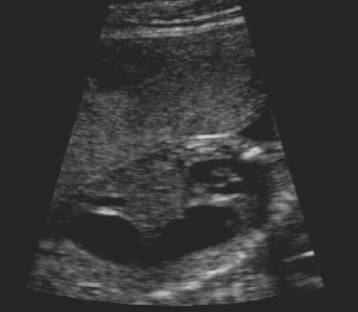

Stomach in left chest cavity

Note the absence of significant cardiac displacement.

This would be unusual in diaphragmatic hernia.